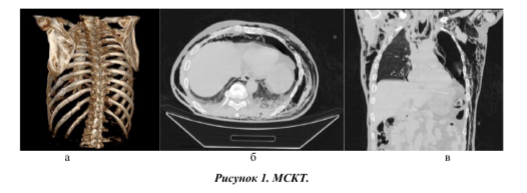

Тяжелая ТОГК. Мультипланарная 3D-peKOH- струкция: поперечный перелом 6, 7, 8, 9, 10 —хребер слева по лопаточной линии, поперечный перелом тел 8, 9, 10ребер слева по средней подмышечной линии (а), аксиальный и фронтальные срезы: ушиб обоих легких, двухсторонний пневмоторакс, двухсторонний гемоторакс, подкожная эмфизема переднезаднебоковой поверхности грудной клетки с двух сторон (а, б).